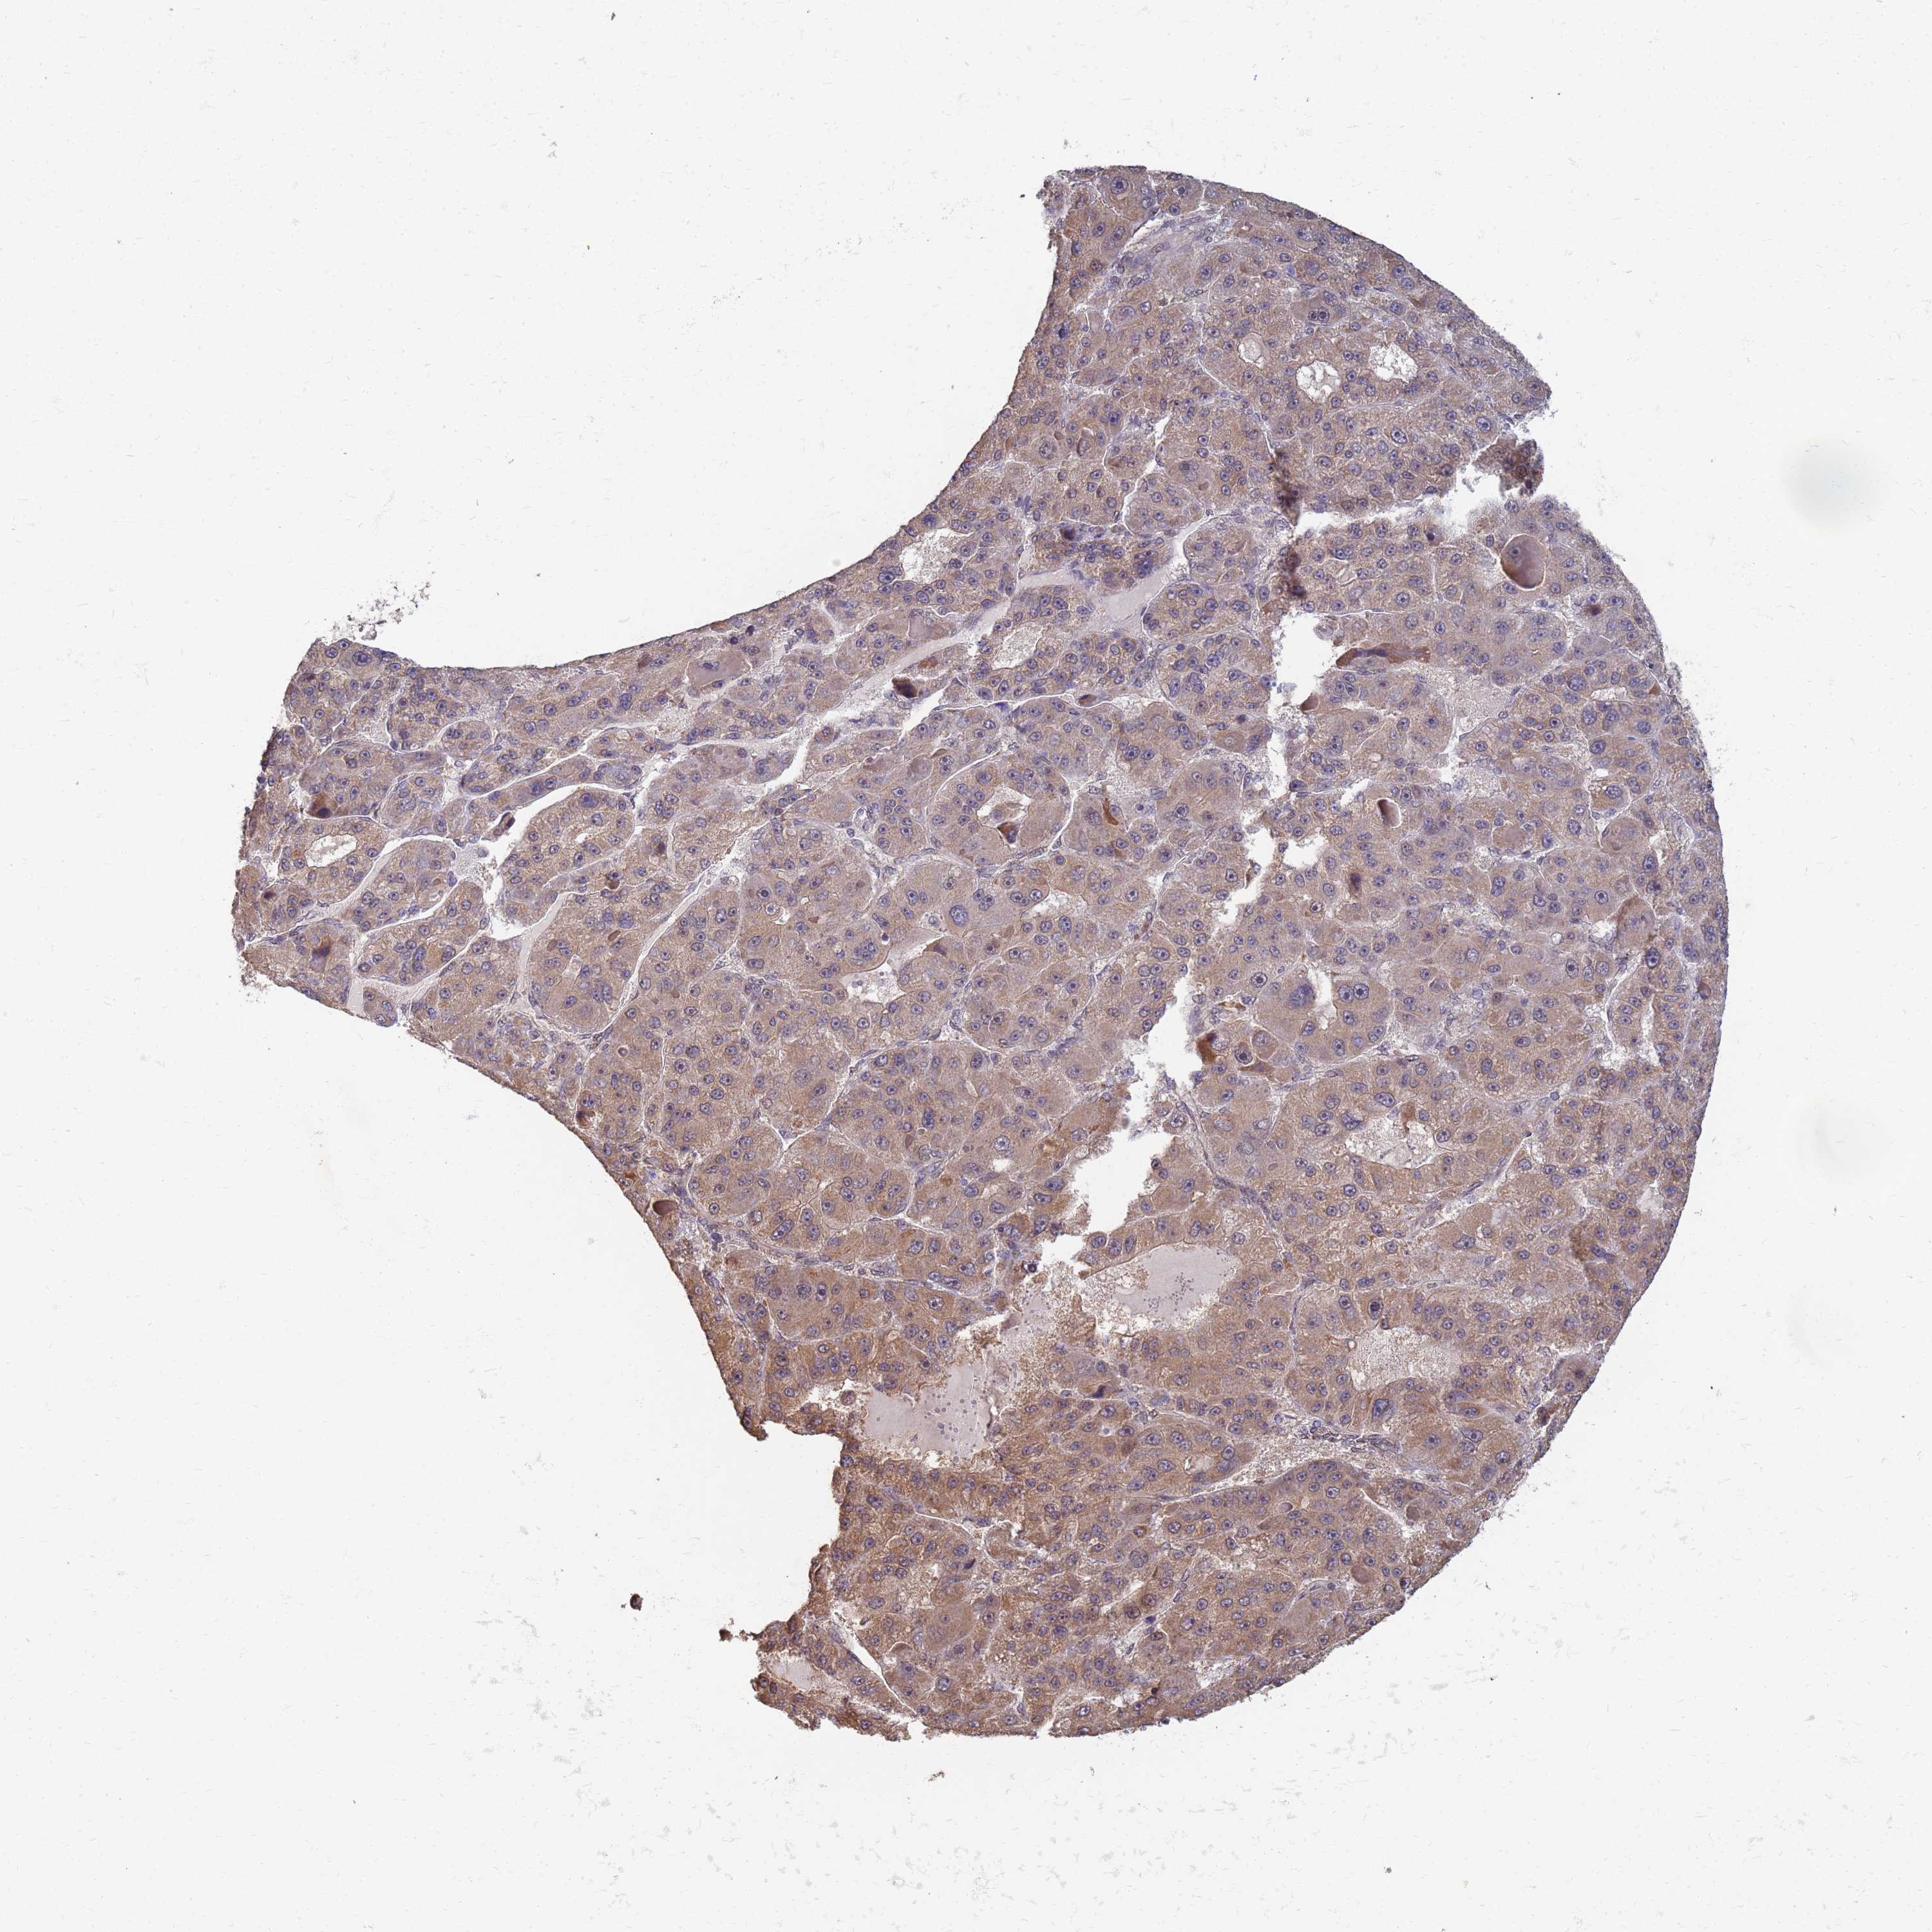

LIVER CANCER - Protein expressioni

A mouse-over function shows sample information and annotation data. Click on an image to view it in a full screen mode. Samples can be filtered based on level of antibody staining by selecting one or several of the following categories: high, medium, low and not detected. The assay and annotation is described here.

Note that samples used for immunohistochemistry by the Human Protein Atlas do not correspond to samples in the TCGA dataset.

Antibody stainingi

Antibody staining in the annotated cell types in the current human tissue is reported as not detected, low, medium, or high, based on conventional immunohistochemistry profiling in selected tissues. This score is based on the combination of the staining intensity and fraction of stained cells.

Each image is clickable and will lead to virtual microscopy that enables deeper exploration of all samples and also displays staining intensity scores, fraction scores and subcellular localization as well as patient and tissue information for each sample.

Antibody HPA036348

Antibody HPA036349

Antibody CAB002422

Antibody CAB005258

Staining

High

Medium

Low

Not detected

Intensity

Strong

Moderate

Weak

Negative

Quantity

>75%

75%-25%

<25%

None

Location

Nuclear

Cytoplasmic/membranous

Cytoplasmic/membranous,nuclear

Cholangiocarcinoma

Carcinoma, Hepatocellular, NOS